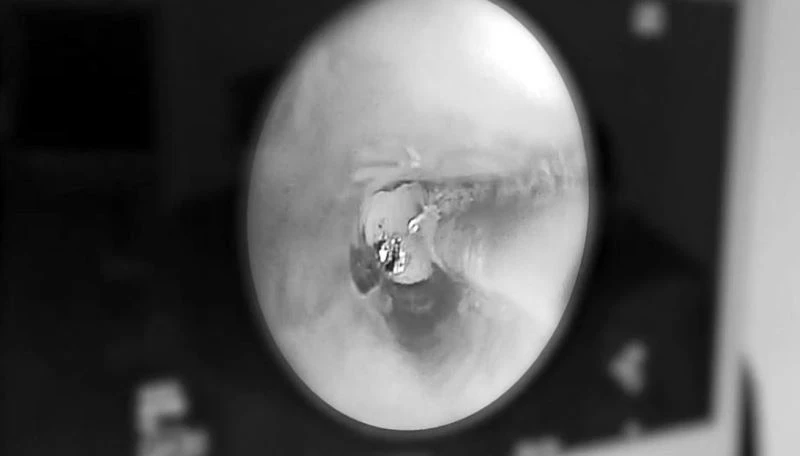

Rezektör balon tedavisinin etkilerinden bahseden Göğüs Cerrahisi Uzmanı Doç. Dr. Hüseyin Ulaş Çınar, “Rezektör balon tedavisi, kronik bronşit nedeniyle oluşmuş KOAH’ta, daralan hava yollarının, üzeri örtülü bir balon yardımıyla genişletilmesi ve beraberinde havayollarında mukus üretimini sağlayan goblet hücrelerinin parçalanarak köpük halinde temizlenmesi işlemidir. Rezektör balon tedavisini genel anestezi altında uyguluyoruz. Yaklaşık 1-2 saat sürüyor. İşlem sonrası 1 gün yoğun bakım ve 1-2 gün takip süresinden sonra hastaları taburcu ediyoruz. Ağır KOAH’ta nefes darlığı nedeniyle yürümekte bile zorlanan hastalar, işlem sonrası günlük yaşamlarına devam edebilecek düzeye geliyorlar. Ancak bu tedavi belli derecenin üzerindeki KOAH hastalarında faydalı olmakta. Hastalığın derecesini fev1 dediğimiz tıbbi terim üzerinden değerlendiriyoruz. Yüzde 80 fev1 değerine sahip hastalar normal kişi olarak değerlendirilebilir. Bu değerin yüzde 50’nin altına düşmesi alarm verici düzeydir. Yüzde 30’un altına düşen hastalar ise bir süre sonra akciğer nakline aday olabilir. Biz yüzde 50’nin altına düşmeyen hastalarda rezektör balon tedavisini düşünmüyoruz. Genel olarak yüzde 30-50 arasında fev1 değeri olan hastalarda uygulanması öneriyoruz” diye konuştu.

Evde yardımcı solunum cihazı olmadan nefes almakta zorlanan hastanın tedavinin hemen sonrasında büyük bir iyileşme kat ettiğini dile getiren Dr. Çınar, “Hastamız 10 yıldır KOAH nedeniyle takip edilen bir hasta. Çeşitli medikal tedavilerle günlük yaşantısını idame ettirmeye çalışıyordu. Oksijen bağımlısı olarak günlük hayatına devam etmek zorundaydı. Son yaptığımız muayenede hastanın fev1 değerinin yüzde 20’nin altına düştüğünü gördük. Akabinde hastanemiz akciğer hastalıkları komitesinin kararı ile rezektör balon tedavisinin yapılmasına karar verdik. Hastamız işlem sonrası 1. günde oksijenden bağımsız bir şekilde günlük aktivitelerini yapacak konuma geldi. İşlem öncesi yüzde 18 olan fev1 değeri, işlem sonrası 12. saate yüzde 44’e kadar yükseldi. Rezektör balon tedavisi gelecekteki KOAH tedavisi açısından umut verici bir tedavi yöntemi. Bu tedavi yönteminin patenti ilk olarak 2006’da bir Türk profesör tarafından alındı. 2010 yılından itibaren de çeşitli kanser hastalıklarının tedavisinde kullanılan bu yöntemin KOAH’ta kullanılmaya başlaması da 2015 yılından itibaren arttı” şeklinde konuştu.